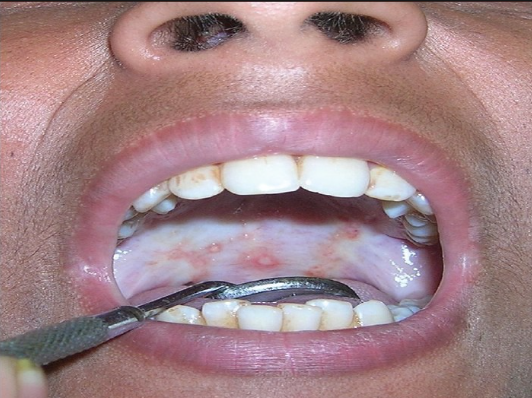

Submucous fibrosis is a potentially debilitating condition characterized by the thickening of oral mucosa, often caused by chewing tobacco or betel nut. At Gindodia Hospital, conveniently located near Datta Mandir Deopur Dhule, we offer specialized care to manage submucous fibrosis and improve oral health.